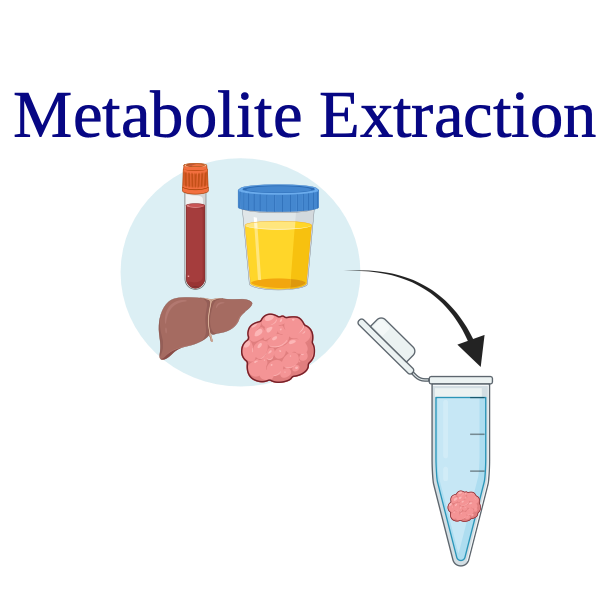

Step (2)

Collect blood, urine, or tissue samples (alternative in-patient NMR)